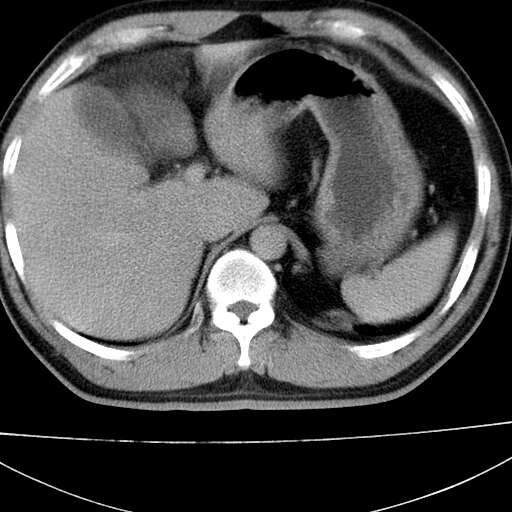

标题: CT21921:腹膜后腔肿物。患者男39Y。体检。增强扫描时间欠准 [打印本页]

标题: CT21921:腹膜后腔肿物。患者男39Y。体检。增强扫描时间欠准

1)考虑左肺下叶后基底段软组织团块,性质待定;建议行进一步检查。2)左肾结石。

左膈肌连续性中断,左侧膈疝可能性大

左下肺隔离症,可见从胸主动脉发出异常血管供应